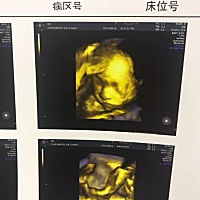

能看出男孩女孩嘛

37周了。这样能看出来是男孩女孩吗